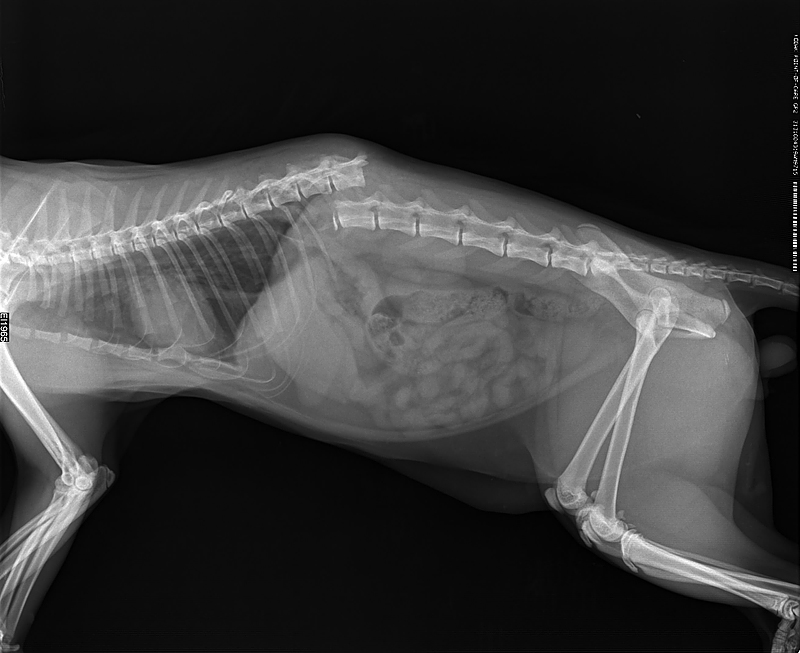

Рентгеновские снимки анатомии собак: строение и здоровье